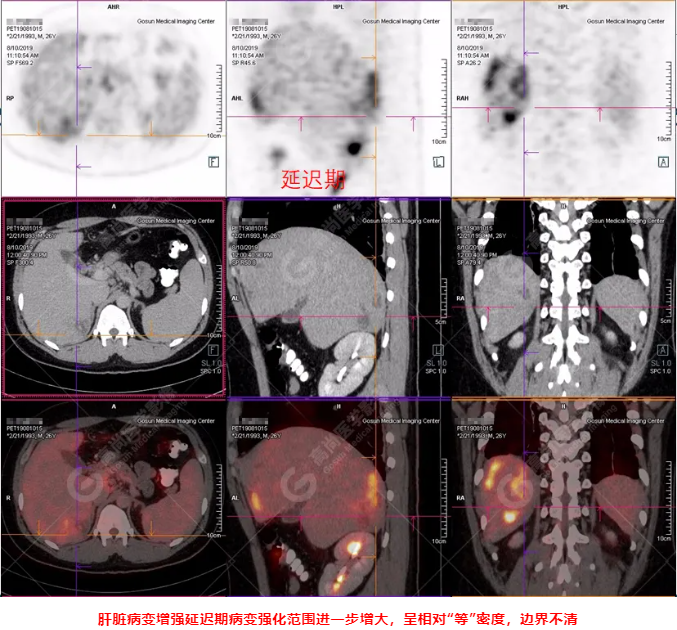

PET/CT全身圖

PET/CT診斷

嗜酸性粒細(xì)胞增多癥肝浸潤(rùn)

吡喹酮治療前兩天體溫驟然升高,之后體溫恢復(fù)正常,半個(gè)月后CT復(fù)查肝臟病變體積較前明顯縮小、吸收。